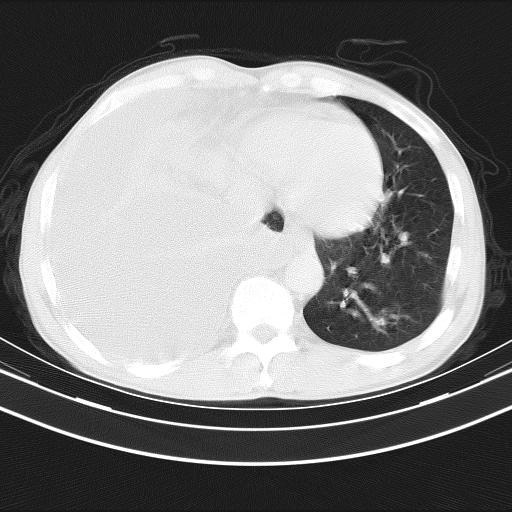

男性,44岁,结核病史多年。现胸闷气短,咳嗽,偶咳血。

右侧胸腔积液

右肺下叶不张

双肺多发结节影最分空洞形成考虑占位不除外结核

双肺陈旧性病变

1、右侧大量胸腔积液伴右肺压缩性膨胀不全,建议抽液治疗后复查 2、两肺继发性tb伴空洞形成。

1)两肺继发性肺结核伴空洞形成,左肺多发性结核球。2)右侧大量胸腔积液伴右肺部分膨胀不全。3)纵隔淋巴结肿大。